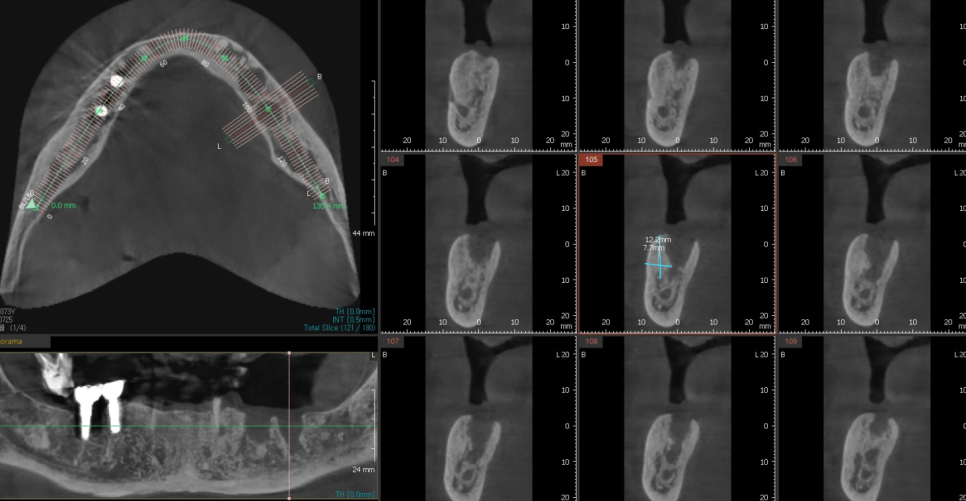

CT를 요래저래 돌려보며

계획을 세워봅니다.

230725

임플란트끼리 연결하여

최소로 식립하되

어금니 개수는 회복할 수 있도록

이렇게 하면 경제적인 부담을 덜어드릴 수가 있죠~